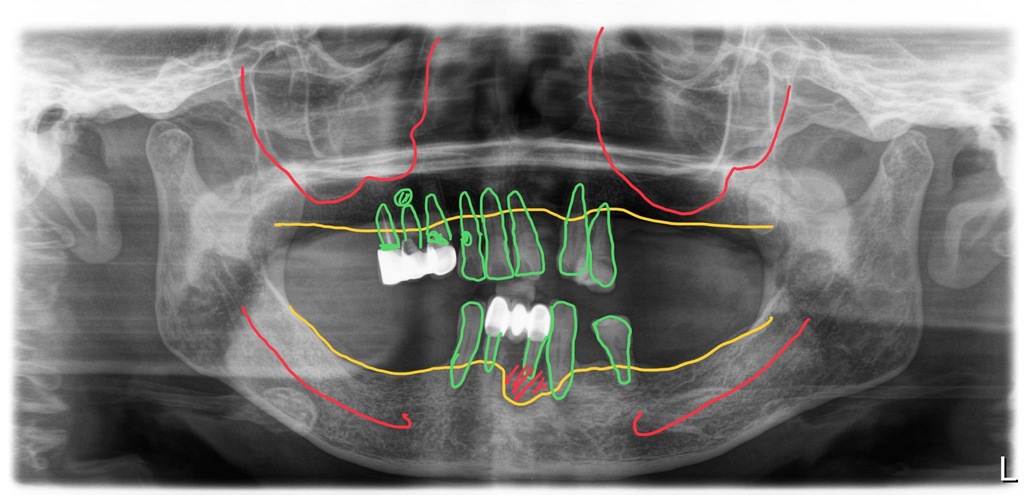

다수의 치아상실

남은 치아들 심한 치주염으로 흔들림

여러 개의 치아들이 이미 상실되어 있었고, 남은 치아들은 치아뿌리의 염증이 있거나 치주염으로 이미 많이 흔들리는 상태였습니다.

그래서 남은 치아 모두 발치를 하고 전체임플란트치료를 계획했습니다. 그리고좌측 상악 구치부의 경우 뼈가 많이 부족해서 상악동 뼈이식도 병행하기로 했어요.